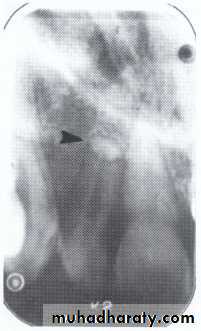

It is a small globule of enamel 1 - 3 mm in diameter

that occurs on the roots of molars (bifurcation ortrifurcation).

It consists of only a nodule of enamel attached to

dentin.

It may have a core of dentin containing pulp horn.

It may cause food stagnation at gingival margin that may predispose to periodontal pocket formation and subsequent

periodontal disease.

if enamel pearl contains pulp, this will be

exposed when pearl is removed.

may be detected on radiographic examination.